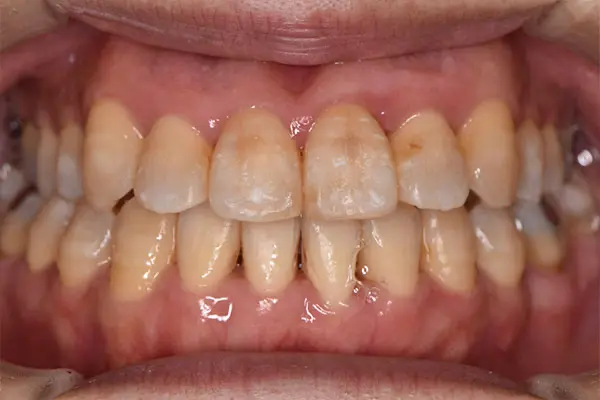

叢生・反対咬合

術前正面

術中正面

術後正面

術前上顎

| 主訴 | 歯のでこぼこ |

|---|---|

| 診断名あるいは主な症状 | 叢生、反対咬合 |

| 初診年齢 | 45歳 |

| 治療内容・装置 | マルチブラケット装置(上下表側からの矯正治療) MSE2 |

| 抜歯・非抜歯 | 下顎左第二小臼歯抜歯 |

| 治療期間 | 2年9ヶ月 |

| 費用 | 882,700円(税込) |

| 治療のリスク・副作用 | 歯の移動に伴う痛み 上下顎前歯部の歯根吸収 装置による口内炎 ブラッシング不良によるむし歯、歯周炎 |